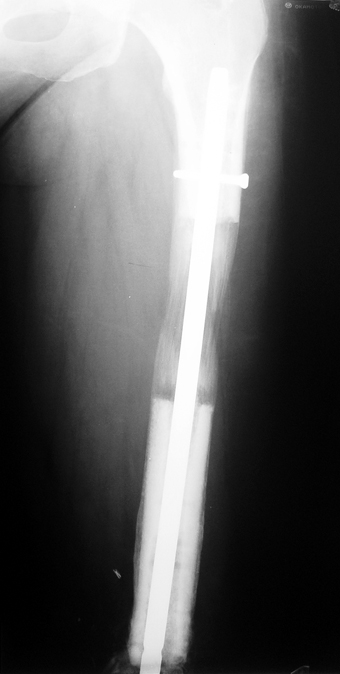

Vaka 3